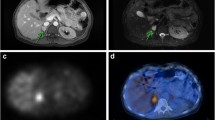

Para-adrenal PGL in a SDHD patient. Axial 18F-FDG PET (a) and PET/CT (b) and 18F-FDOPA PET (d) and PET/CT (e). 18F-FDG PET was positive, while 18F-FDOPA PET was considered as falsely negative. Gross pathology showed that the tumor was developed from para-adrenal paraganglia (adr adrenal, pgl paraganglioma) (c)

HIF2A-related paraganglioma of the organ of Zuckerkandl. Contrast-enhanced CT arterial phase (a) showing a hypervascular and heterogeneous left para-aortic mass located at the level of the inferior mesenteric artery (arrow). 18F-FDOPA PET/CT (b) and 18F-FDG PET and PET/CT (c) showing a single tumor with heterogeneous uptake and a preferential 18F-FDOPA imaging pattern, a finding which is opposite to the classical SDHx-associated imaging phenotype (see Fig. 14.7)